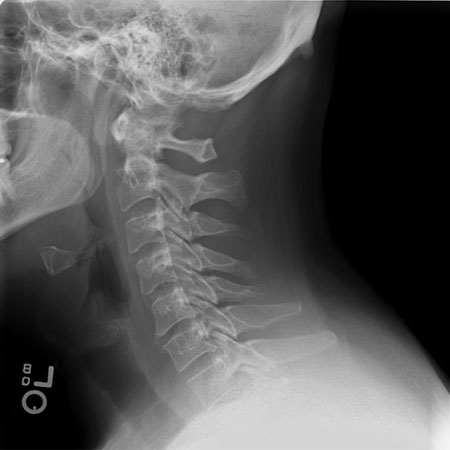

Cervical spondylosis (osteoarthritis of the spine, which includes the spontaneous degeneration of either disc or facet joints) is an almost universal finding with increasing age.[15] Only a subset of patients present with axial neck pain; many patients are asymptomatic.[16][17][Figure caption and citation for the preceding image starts]: Normal lateral cervical spine x-rayWith permission of the University of Colorado Department of Radiology [Citation ends].